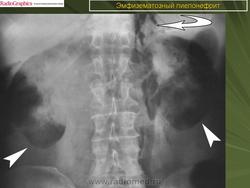

ID: 21473 Emphysematous pyelonephritis - on xray Dr MT Niknejad - 25 Jan 2013 The findings of the abdominal xray are consistent of emphysematous pyelo...

Эмфизематозный пиелонефрит

Случаи и цифры